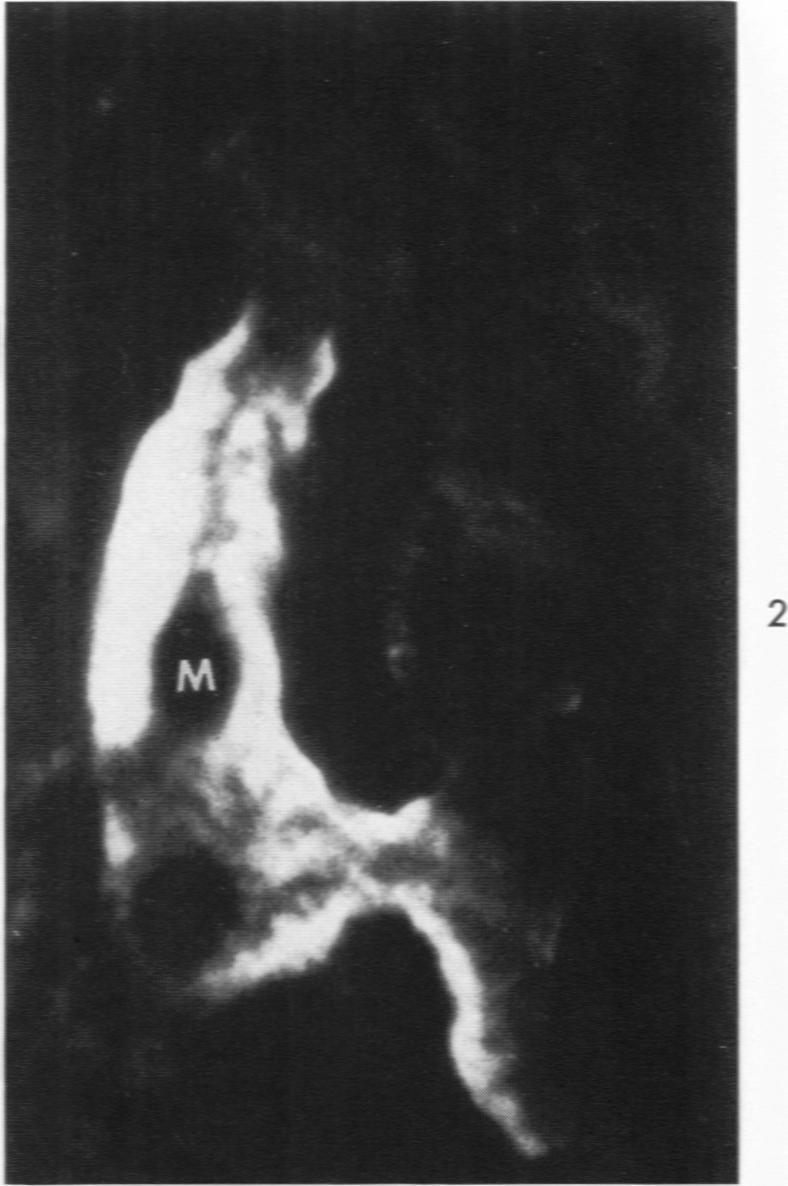

Experimental autoimmune nephrosis in rats. Morphogenesis of the glomerular lesion: immunohistochemical and electron microscopic studies.

Am J Pathol. 1969 Jan;54(1):47-71.

Experimental autoimmune nephrosis in rats. Morphogenesis of the glomerular lesion: immunohistochemical and electron microscopic studies.大鼠实验性自身免疫性肾病。肾小球病变的形态发生:免疫组织化学和电子显微镜研究。